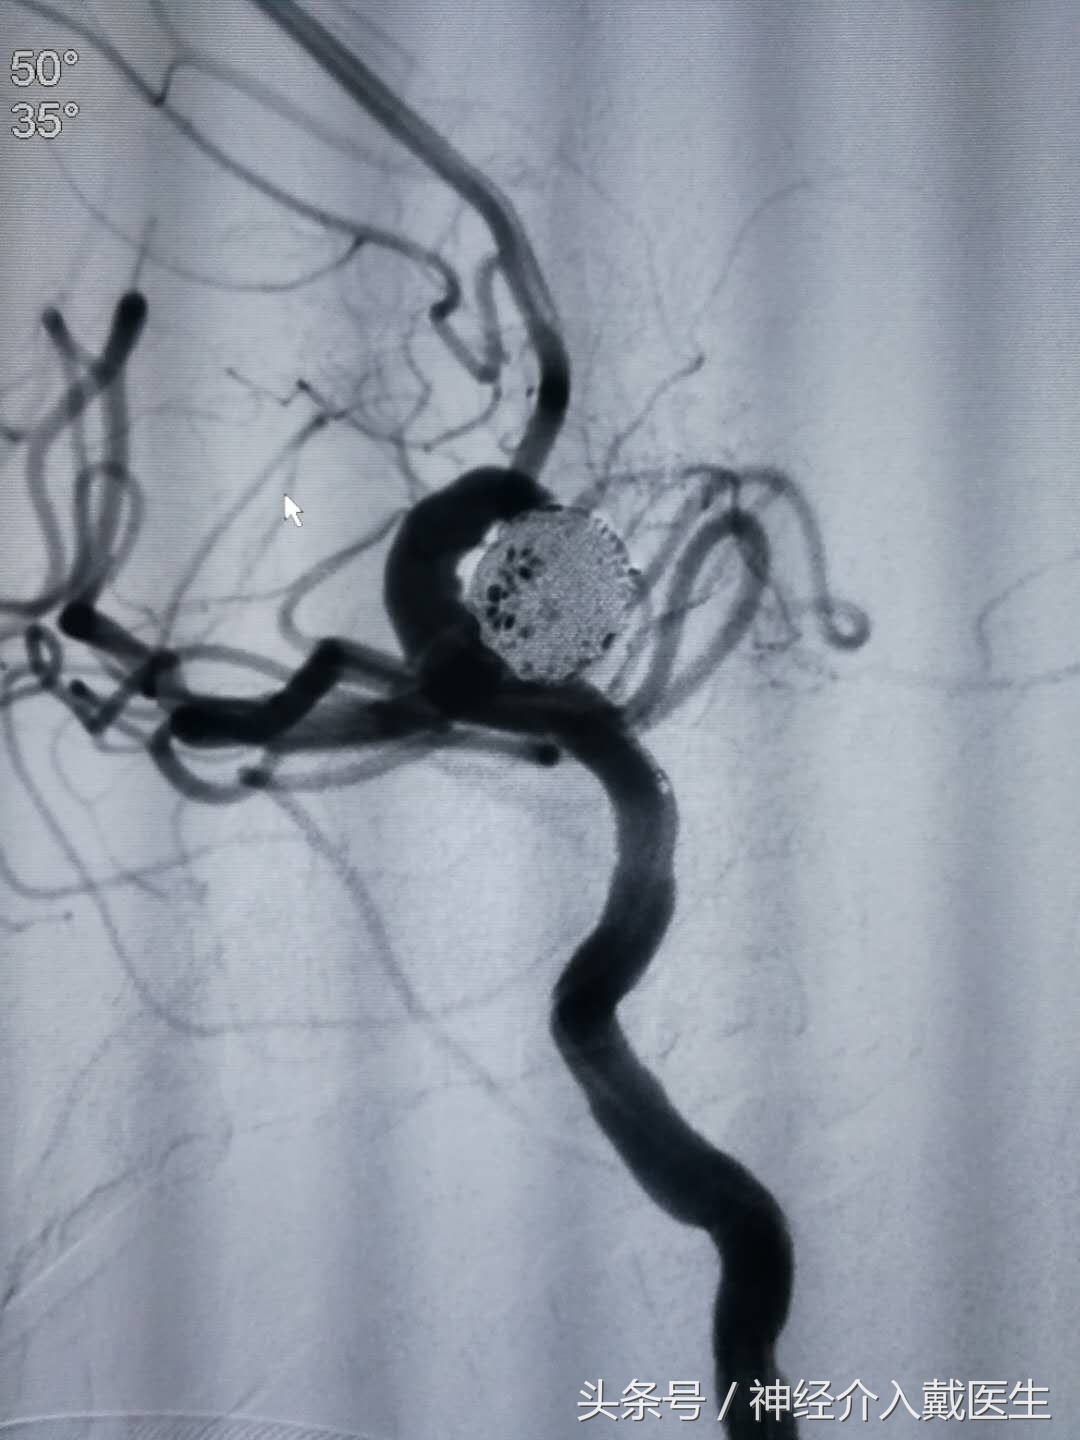

选好工作位置

第一个弹簧圈用的的EV3的3D成篮弹簧圈,Axium_3D,12mm*40cm,成篮弹簧圈的效果,成篮满意。

依次选择国产维心弹簧圈,10mm*30cm,9mm*30cm,7mm*30cm*2个,6mm*20cm后造影效果,载瘤动脉通畅。

释放收尾弹簧圈效果。